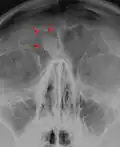

Остеома лобной пазухи на рентгене

Остеома лобной пазухи на компьютерном томографе